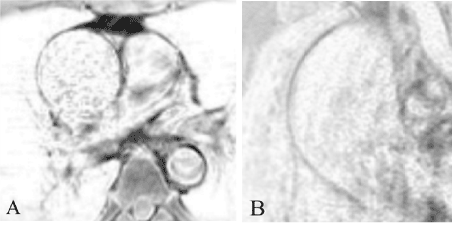

Figure 2. T1-SE (A) axially (in the middle third of the aortic aneurysm) and T1-SPIR-black blood (B) in the oblique plane. Thinned aortic wall, more defined in the central part

In the cine-SSFP view, we were able to clearly visualize the aortic wall's movement during the cardio cycle and blood flow direction. The QFlow sequence can be used to quantify the pulse wave velocity in an aneurysm or if aortic valve function is required. To examine the ascending aorta wall's thickness and vascularization, T1-SE-GRE in the axial plane, T1- fat-selective radiofrequency pulse and spoiler-black-blood (Figure 3), and T2- fat-selective radiofrequency pulse and spoiler-black-blood in the axial and oblique planes were performed.

According to the MRI conclusion, the patient has an enlarged ascending aorta from the root for up to 9 cm, with a maximum diameter of up to 5.5 cm. The patient needs surgery [4,5]. The wall in the aneurysm is evenly thinned, more defined in the middle part, the pulsation is reduced, with signs of dyskinesia, from the edge of the aneurysm to the orifice of the brachiocephalic trunk – the aortic wall is intact (Figure 4) within no more than 3 cm, the aortic diameter at this level is no more than 3.5 cm. Additionally, the patient has a bicuspid aortic valve. Dissection, thickening, and hypervascularization of the thoracic aorta wall and the proximal parts of its main branches were not revealed. The orifice of the main branches was typical anatomy.

Figure 4. T1-SPIR-BB imaging, axial plane (A) immediately after distal aneurysm edge of ascending aorta; oblique plane (B) before orifice of the brachiocephalic trunk. The intact thickness of the aortic wall (arrows)